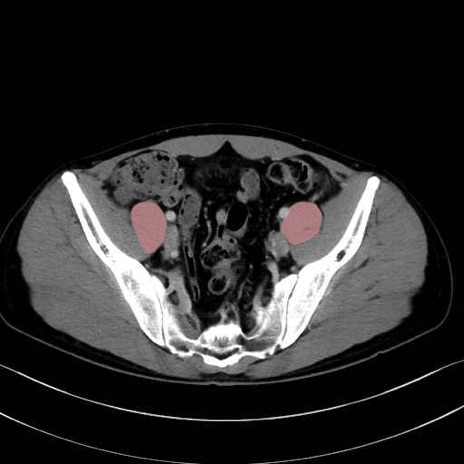

2. 腸腰筋群と骨盤底筋

大腰筋 (Psoas major)

腸骨筋 (Iliacus)